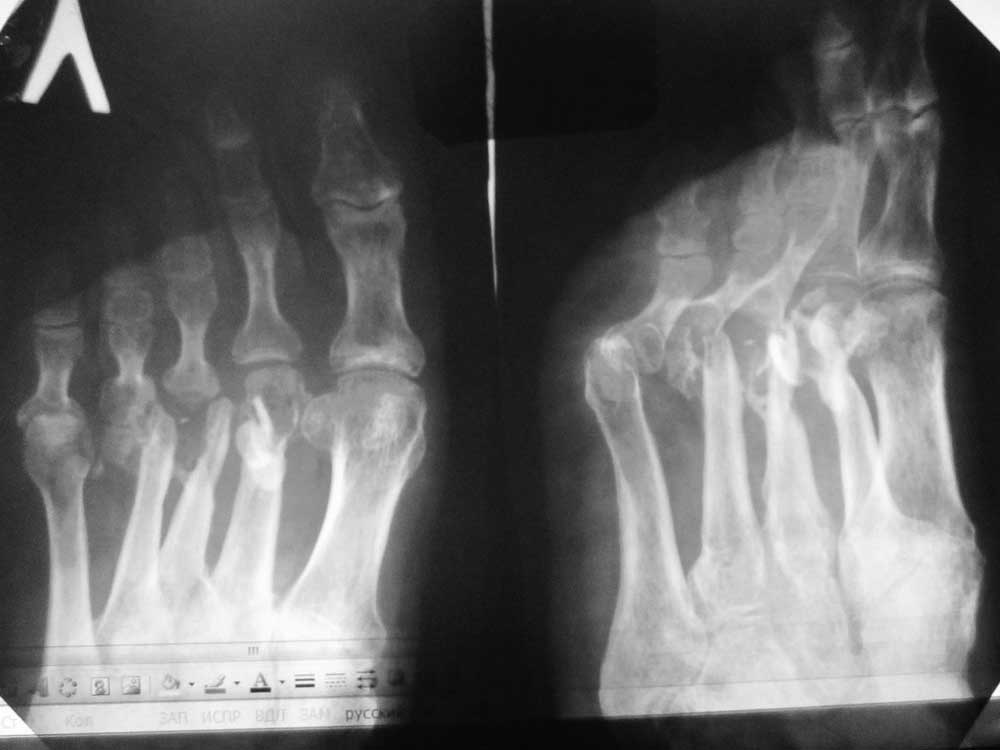

Больной 45 лет, мужчина. Оперирован спицами в мае 2013 года в Таджикистане по поводу открытых переломов 2-4 плюсневых костей. Спицы были удалены со слов больного через 2 недели, после чего он был выписан на амб. долечивание, приступил к дозированной нагрузке. В сентябре 2013 года открылся свищевой ход на тыле стопы в 3-м межплюсневом промежутке. Больной лечился самостоятельно различными антибиотиками. Рассматривается секвестрнекрэктомия головок и части диафизов 2-4 плюсневых костей, проточно-промывное дренирование+спейсер с ванкомицином (или без спейсера), а затем в холодном периоде – костная аутопластика.Возможно после секвестрнекрэктомии появится избыточная подвижность 2-4 пальцев – чем и как посоветуете фиксировать??